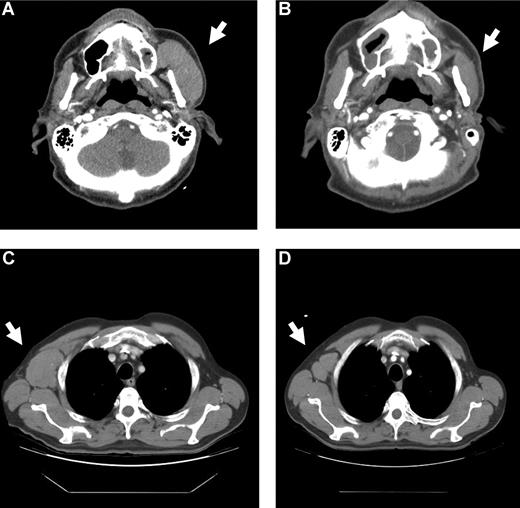

Patient 0414 had failed prior therapy for multiply relapsed mantle cell NHL before undergoing matched unrelated donor allo-HCT. Upon RM after allo-HCT, he received 2 DLI without evidence of disease response. He had rapidly growing left parotid and right axillary masses before enrollment on study. Administration of ipilimumab was followed approximately 4 weeks later with a febrile illness that was associated with significant clinical and radiologic regression of his lymphoma resulting in a partial remission (PR) that was persistent at 2 months after ipilimumab (Figure 2). At 3 months after ipilimumab, the responses in the parotid and axillary masses were maintained, but the patient developed a new positron emission tomography (PET)–avid lesion within the abdomen. The patient was then taken off the study to pursue alternative therapeutic options.

Regression of malignancy in a patient with mantle cell lymphoma. CT scans from patient 0414 (dose level 1.0 mg/kg) showing left parotid (A,B), and right axillary (C,D) nodal masses before (A,C) and 1 month after (B,D) ipilimumab infusion.